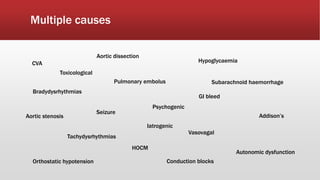

This document discusses various cases of collapse and syncope. It defines collapse as transient loss of consciousness with loss of postural tone and full recovery. Syncope is defined as loss of postural tone with or without loss of consciousness and full recovery. It then discusses the multiple potential causes of collapse and syncope including toxicological, cardiac conduction abnormalities, structural cardiac issues, autonomic dysfunction and more. It then goes through 9 case examples, discussing important questions to ask, potential tests and interventions for each case.